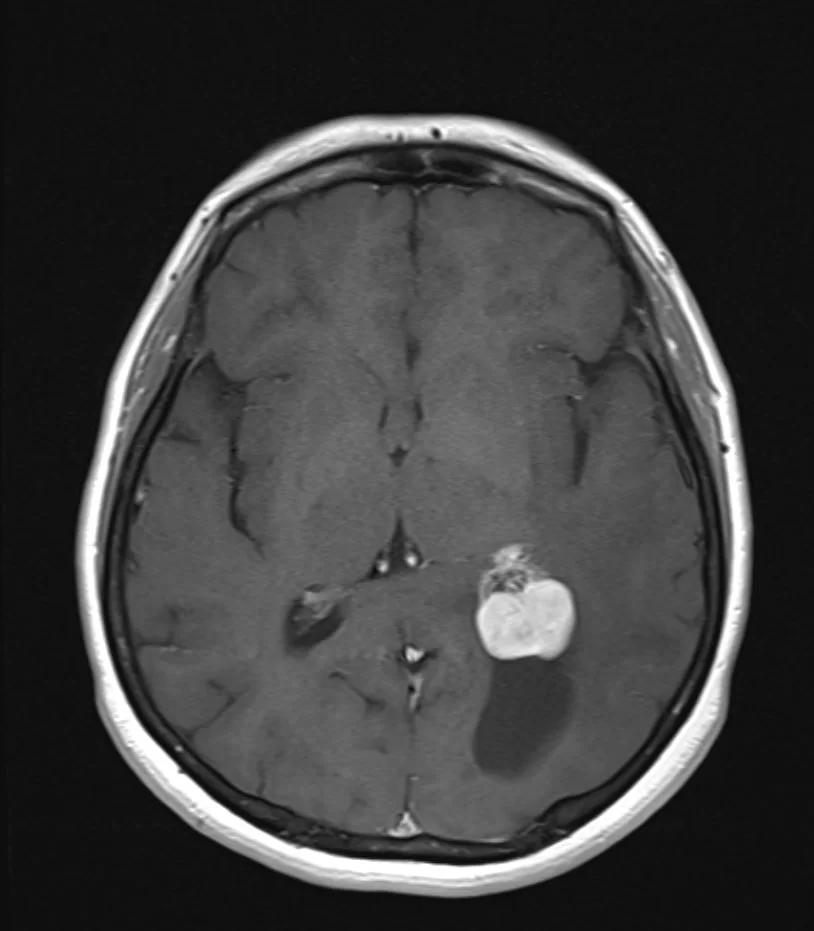

Ασθενής άνδρας, 31 ετών με επεισόδια κεφαλαλγίας. H Μαγνητική Τομογραφία εγκεφάλου ανέδειξε εκτεταμένη χωροκατακτητική εξεργασία δεξιά κροταφικά με πίεση επί του σύστοιχου κροταφικού κέρατος και

Περισσότερα